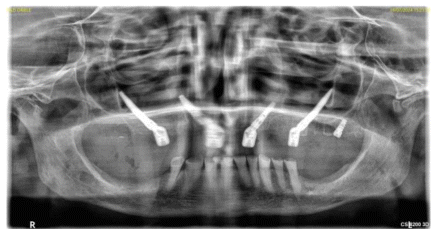

Intraoral examination and panoramic radiographic assessment (Figures 1 and 2) indicated the need for implant-prosthetic rehabilitation treatment.

After analyzing the second-level radiographic examination, specifically the CBCT scan, and in agreement with the patient, it was decided to fulfill his specific request to perform a fixed prosthetic rehabilitation with implant support.

To achieve optimal implant-prosthetic rehabilitation given the severe maxillary atrophy, it was decided to perform a Hybrid Zygoma intervention with the insertion of two zygomatic implants, two paranasal implants in regions 1.2 and 2.2, and a pterygoid implant in the second quadrant.

A follow-up CBCT scan was performed two years after surgery. The Schneiderian membrane showed physiological ventilation with no signs of inflammation (Figure 6).